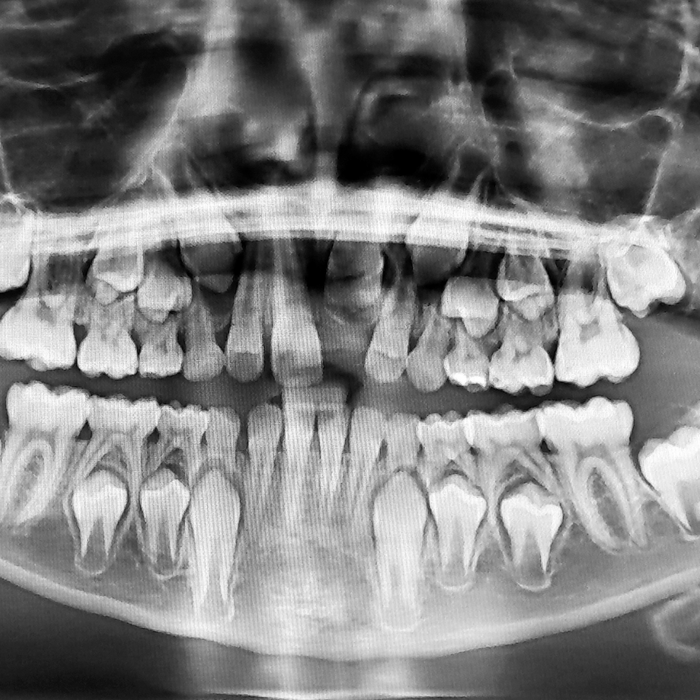

Pediatric Dentistry